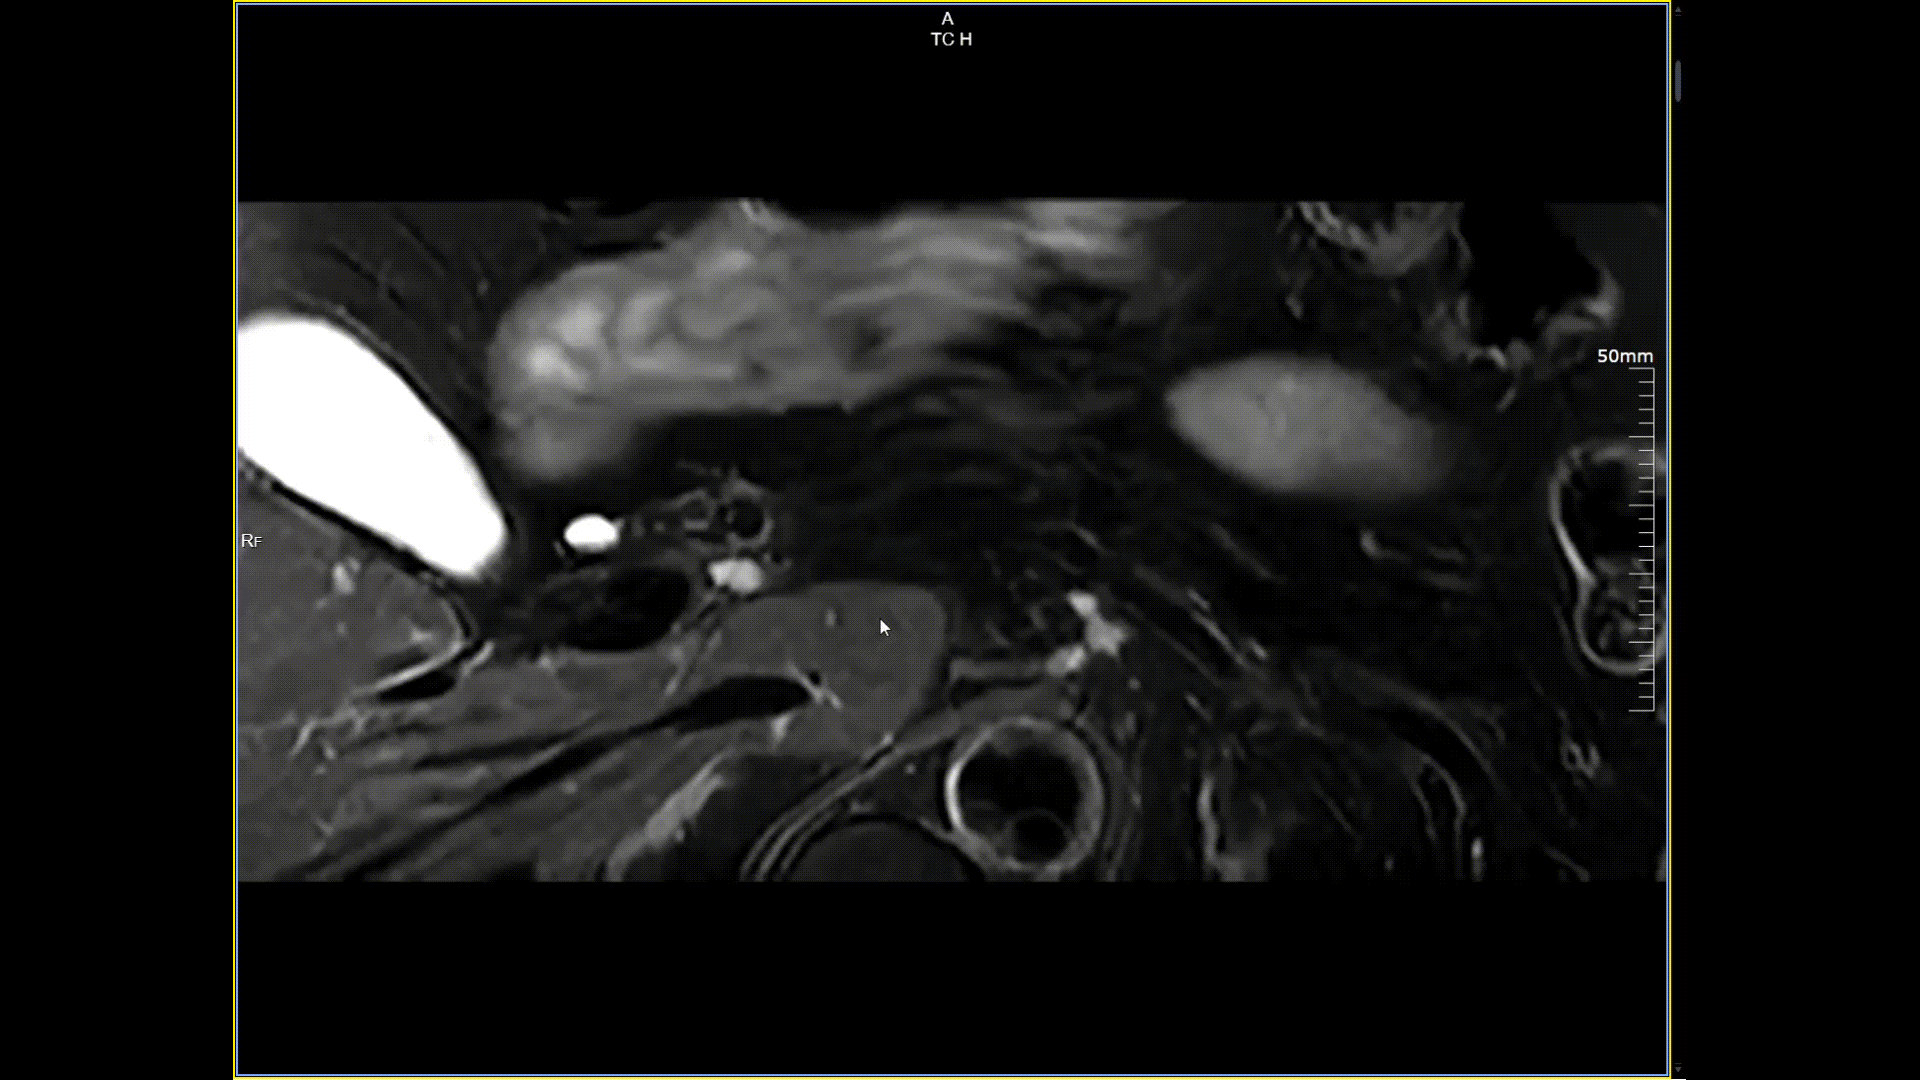

胰腺小视野高分辨,分辨率0.5*0.5mm

5.0T磁场强度远高于其他设备,使得氢原子核在磁场中的响应信号极大地增强。这就像在安静的房间里能听清细微的声音一样,高信噪比能让医生看到更微小、更模糊的病变结构。例如上述患者的检查,该设备可以呈现0.2x0.2毫米高分辨率的图像以及动态显示血管走行,使得病变血管的细微解剖结构、分布及其与周边脑组织的关系得以直观呈现,为临床医生进行精准诊断并制定后续治疗方案提供了重要的影像学依据。

相比目前临床广泛使用的1.5T和3.0T核磁共振设备,5.0T核磁共振的优势十分显著。该设备能为患者带来更早、更精准的诊断,有效规避漏诊与误诊,助力患者及时接受规范治疗以显著改善预后,尤其对于恶性肿瘤和神经系统疾病,早期精准诊断更能重塑患者生命轨迹。同时,依托其提供的精确病灶信息,医生可制定“量身定制”的手术、放疗或药物治疗方案,实现疗效最大化与副作用最小化。作为连接临床与科研的桥梁、推动医学进步的强大引擎,5T技术还支持实时观察疾病微观演化过程以探索疾病新机制,并凭借卓越的功能和代谢成像能力,开发可用于疾病早期诊断、分型及疗效预测的新型成像生物标志物。